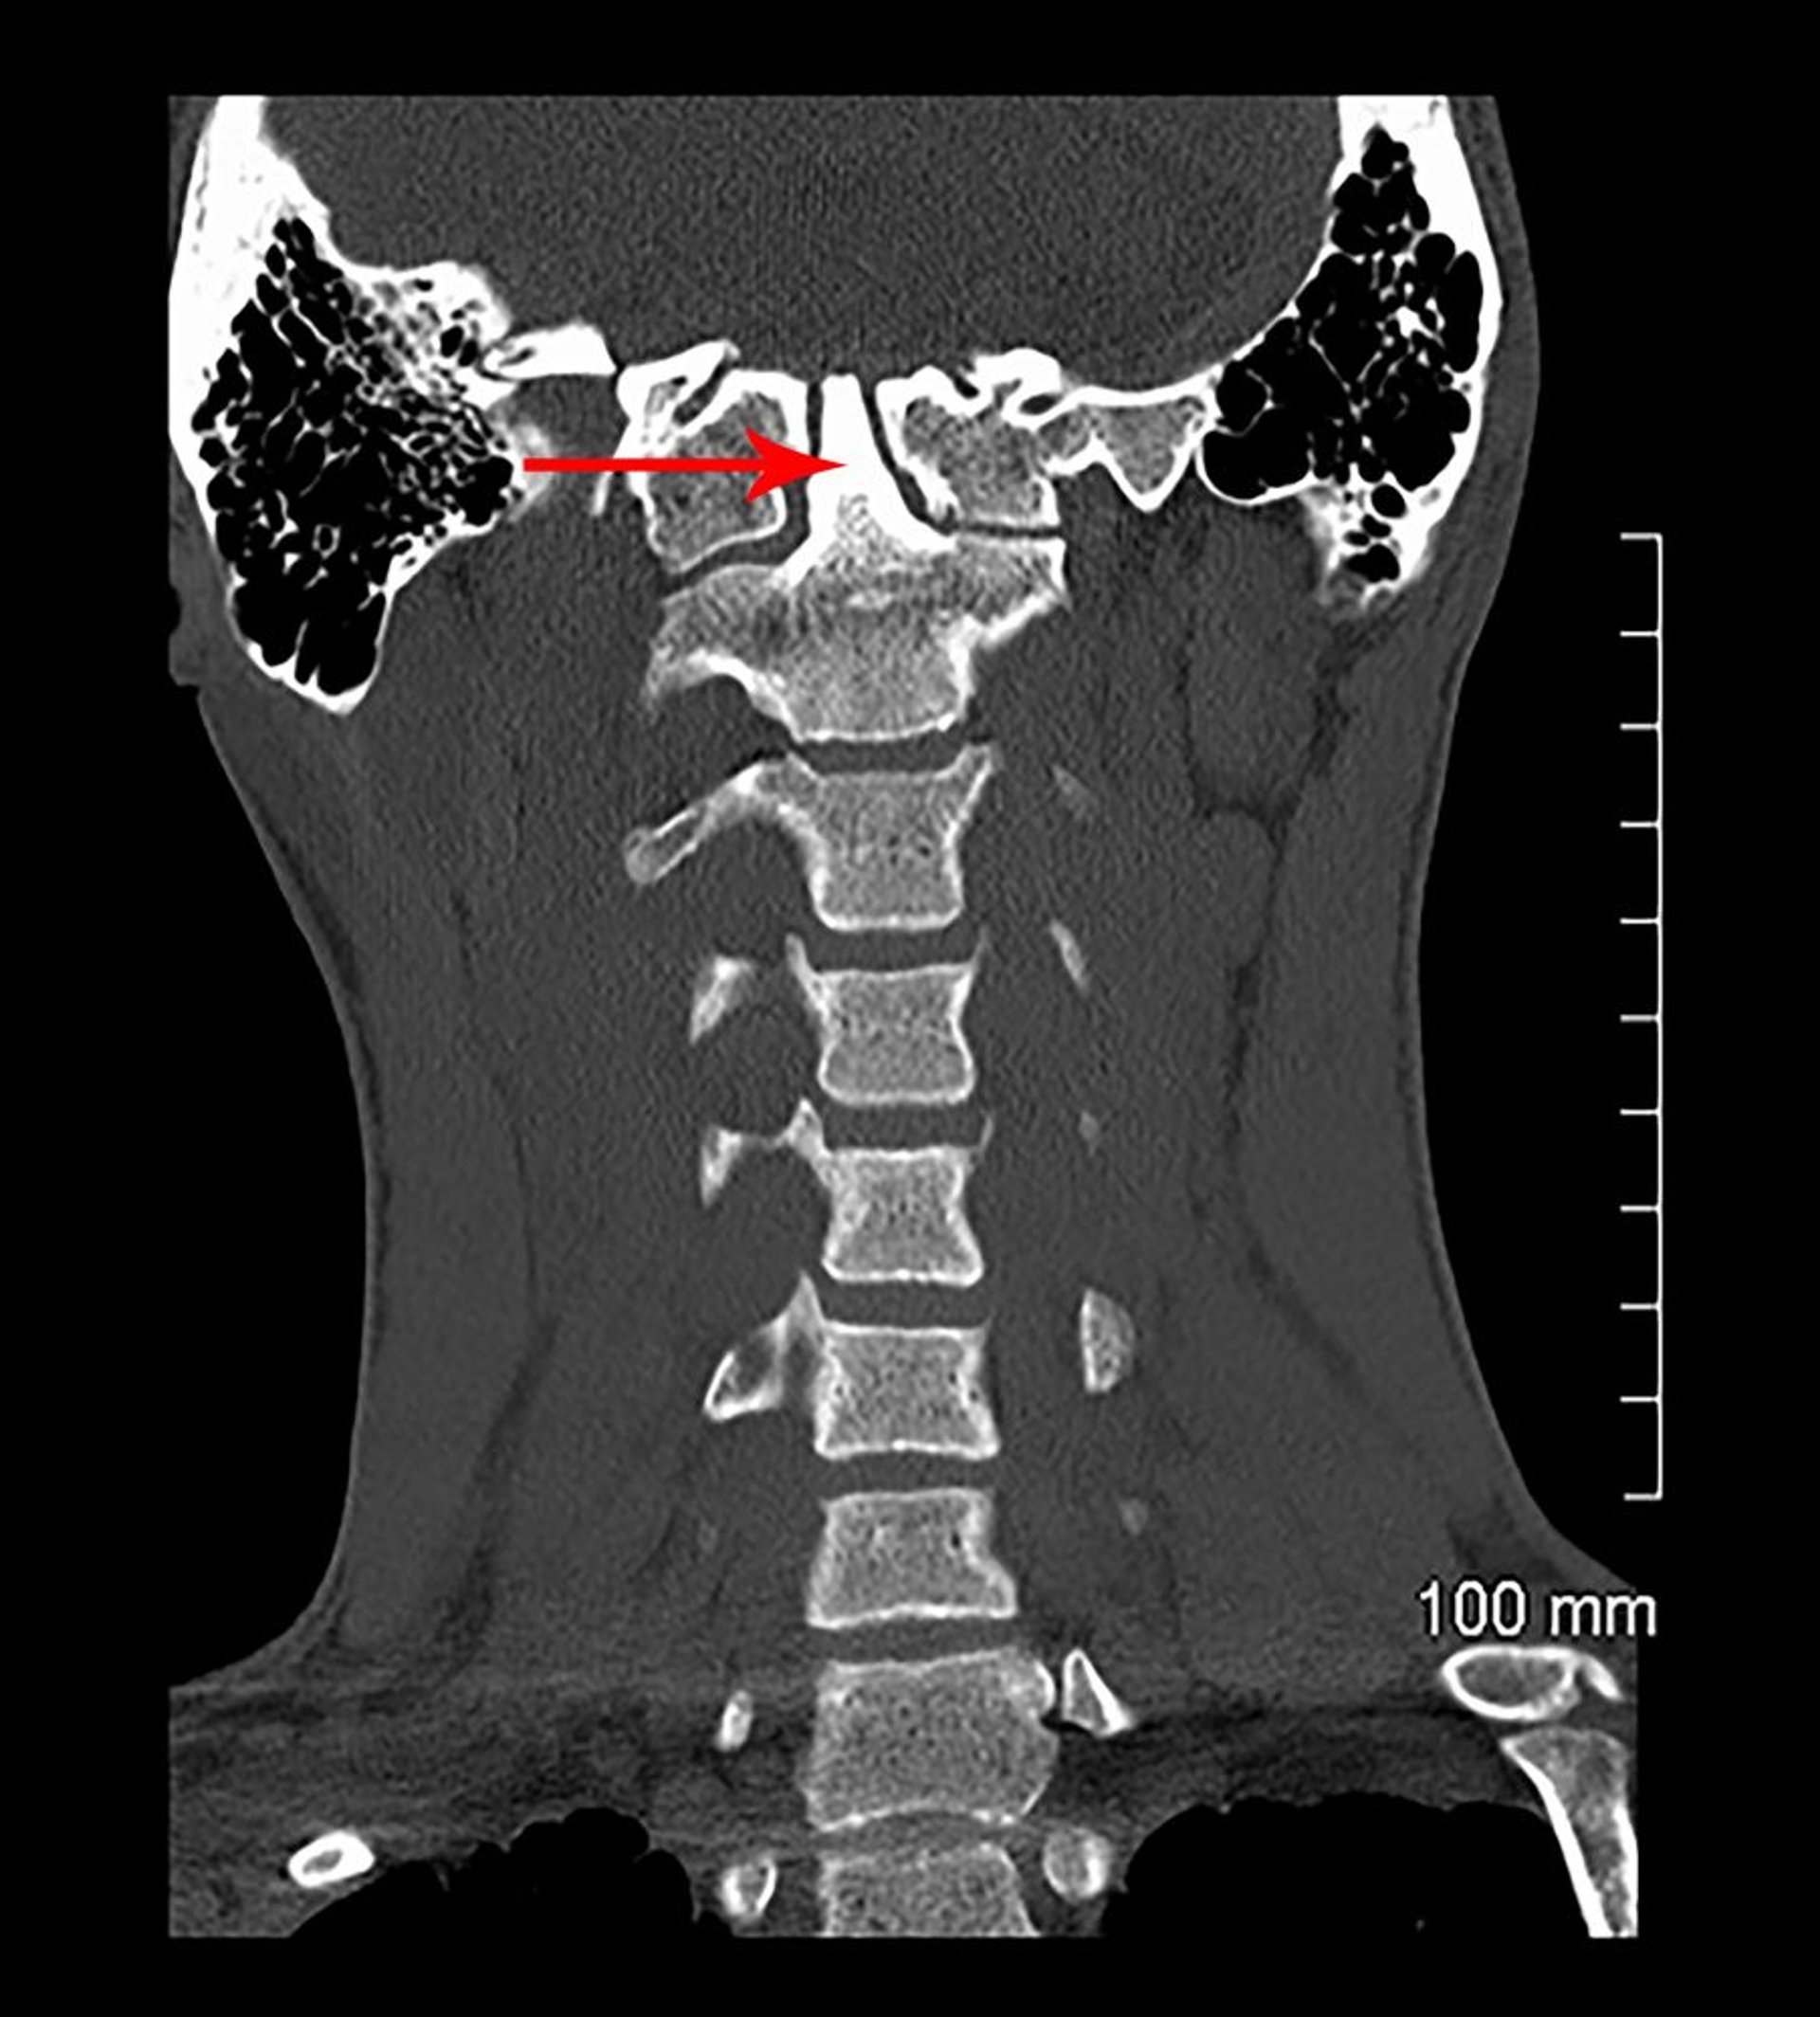

Платибазия и врожденная ассимиляция атланта (КТ)

На данном снимке КТ во фронтальной проекции позвонок С1 сливается с основанием черепа (врожденно). Зубовидный отросток эпистрофея (отмечен стрелкой) простирается на основание черепа (базилярная инвагинация).